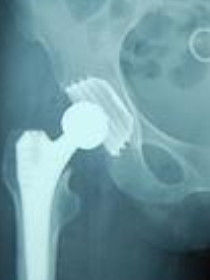

③股骨頸頭下型骨折:此類癒合困難,常發生壞死,對65歲以上老年人多施行人工關節置換。對此年齡以下者,宜選擇多枚針或加壓釘內固定。

⑥帶鏇髂深血管蒂的髂骨瓣轉位移植治療股骨頸骨折:可用於青壯年新鮮股骨頸骨折。手術顯露股動脈,直接在腹股溝韌帶下找尋鏇髂深血管。以此血管束為中心,設計取6.0cm×1.5cm×1.5cm全層骨塊,用鹽水紗布包繞骨塊待用。人工股骨頭置換術:對年齡超過65~70歲以上新鮮股骨頸頭下或粉碎性骨折有移位者,陳舊性骨折不癒合或股骨頭已壞死而髖臼無骨關節炎者,可行人工股骨頭置換手術。